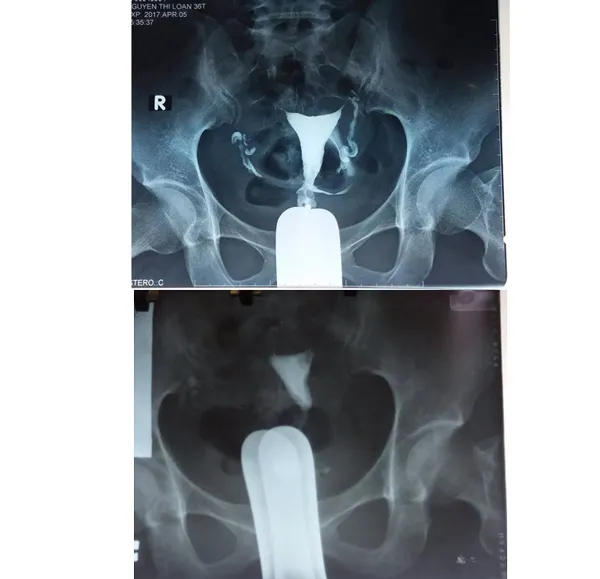

Kỹ thuật “Nong vòi tử cung bằng catheter qua nội soi buồng tử cung kết hợp với nội soi ổ bụng” sẽ giúp những phụ nữ bị tắc vòi tử cung đoạn kẽ không cần phải thụ tinh trong ống nghiệm mà vẫn có thể mang thai tự nhiên.

(SGGP).- Kỹ thuật “Nong vòi tử cung bằng catheter qua nội soi buồng tử cung kết hợp với nội soi ổ bụng” sẽ giúp những phụ nữ bị tắc vòi tử cung đoạn kẽ không cần phải thụ tinh trong ống nghiệm mà vẫn có thể mang thai tự nhiên.

Theo GS-TS Nguyễn Viết Tiến, trước đây, những bệnh nhân bị bệnh lý vòi tử cung như tắc tử cung đoạn kẽ phải thực hiện các phương pháp như nội soi, tạo hình tử cung nhưng hiệu quả không cao, nguy cơ với bệnh nhân rất lớn. Vì vậy, những bệnh nhân này thì chỉ có cách thực hiện thụ tinh trong ống nghiệm. Tuy nhiên, không phải ai cũng có điều kiện để làm thụ tinh trong ống nghiệm và nhiều khi chất lượng trứng không còn tốt nên tỷ lệ thành công thấp. Do đó, với kỹ thuật mới nói trên, lần đầu tiên áp dụng tại Việt Nam, sẽ giúp cho nhiều phụ nữ hiếm muộn được làm mẹ với chi phí rất thấp. Hơn nữa, kỹ thuật này có thể chuyển giao cho các cơ sở khám chữa bệnh khác để bệnh nhân bị bệnh tắc vòi trứng, nhất là ở đoạn kẽ, có cơ hội được phẫu thuật để mang thai tự nhiên.

Thống kê của Trung tâm Hỗ trợ sinh sản quốc gia, tỷ lệ vô sinh, hiếm muộn ở nước ta ngày càng tăng, trong đó nguyên nhân do người vợ chiếm một nửa. Trong số các bệnh lý gây hiếm muộn thì vòi tử cung là nguyên nhân thường gặp nhất chiếm từ 43% - 59%, trong đó, vô sinh do tắc đoạn gần vòi tử cung chiếm tới 25%.